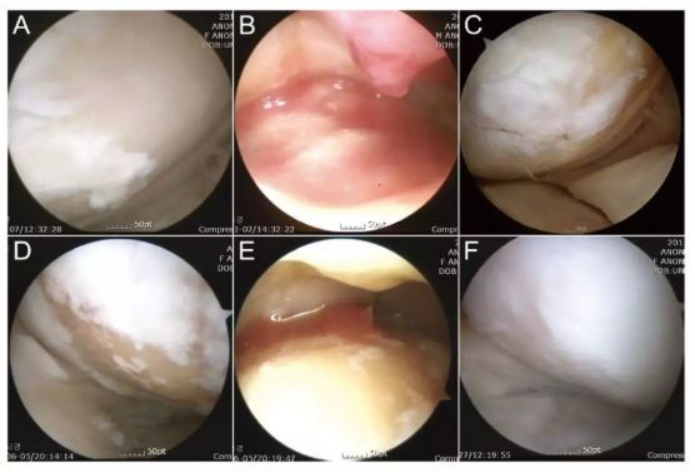

下图中A-C为51岁男性膝关节镜,,D-F为54岁女性膝关节镜。。。。A/D为治疗前,,,,白色示意软骨,,,,浅黄色示意裸露的骨。。B/E为间充质干细胞注射。。C/F为治疗后的关节镜检查。。